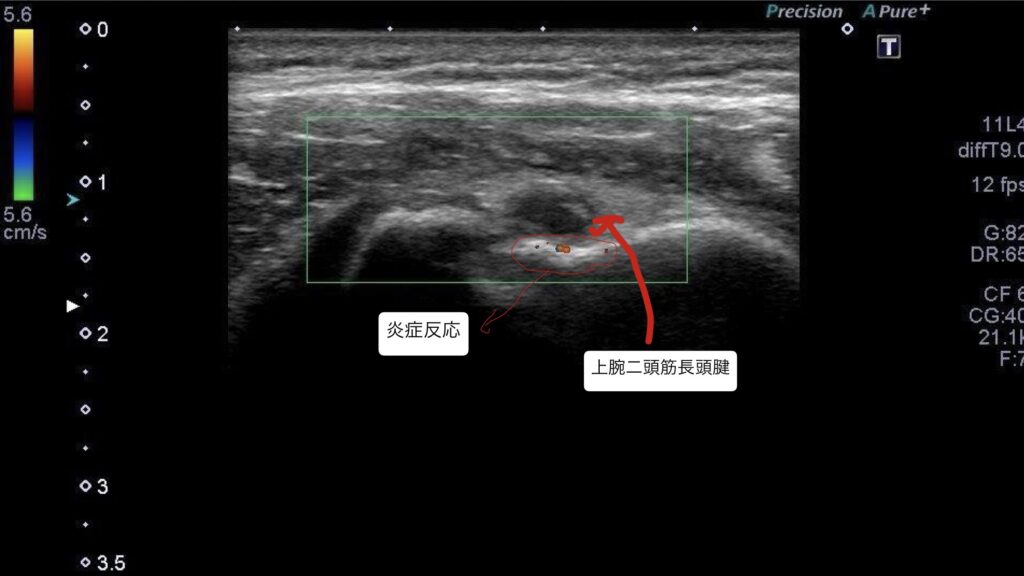

・超音波エコーで観察したところ、上腕二頭筋長頭腱周囲の炎症反応を確認した。

・初回は上腕二頭筋長頭腱の炎症鎮静と筋緊張の緩和を目的に超音波エコーガイド下で鍼施術を行った。